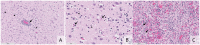

Avian influenza H5N1 is a highly pathogenic virus that primarily affects birds. However, it can also infect other animal species, including mammals. We report the infection of nine juvenile red foxes (Vulpes vulpes) with Highly Pathogenic Avian Influenza A type H5N1 (Clade 2.3.4.4b) in the spring of 2022 in the central, western, and northern regions of New York, USA. The foxes displayed neurologic signs, and examination of brain and lung tissue revealed lesions, with brain lesions ranging from moderate to severe meningoencephalitis. Analysis of tissue tropism using RT-PCR methods showed a comparatively lower Ct value in the brain, which was confirmed by in situ hybridization targeting Influenza A RNA. The viral RNA labelling was highly clustered and overlapped the brain lesions, observed in neurons, and grey matter. Whole viral genome sequences obtained from the affected foxes were subjected to phylogenetic and mutation analysis to determine influenza A clade, host specificity, and potential occurrence of viral reassortment. Infections in red foxes likely occurred due to preying on infected wild birds and are unlikely due to transmission between foxes or other mammals.